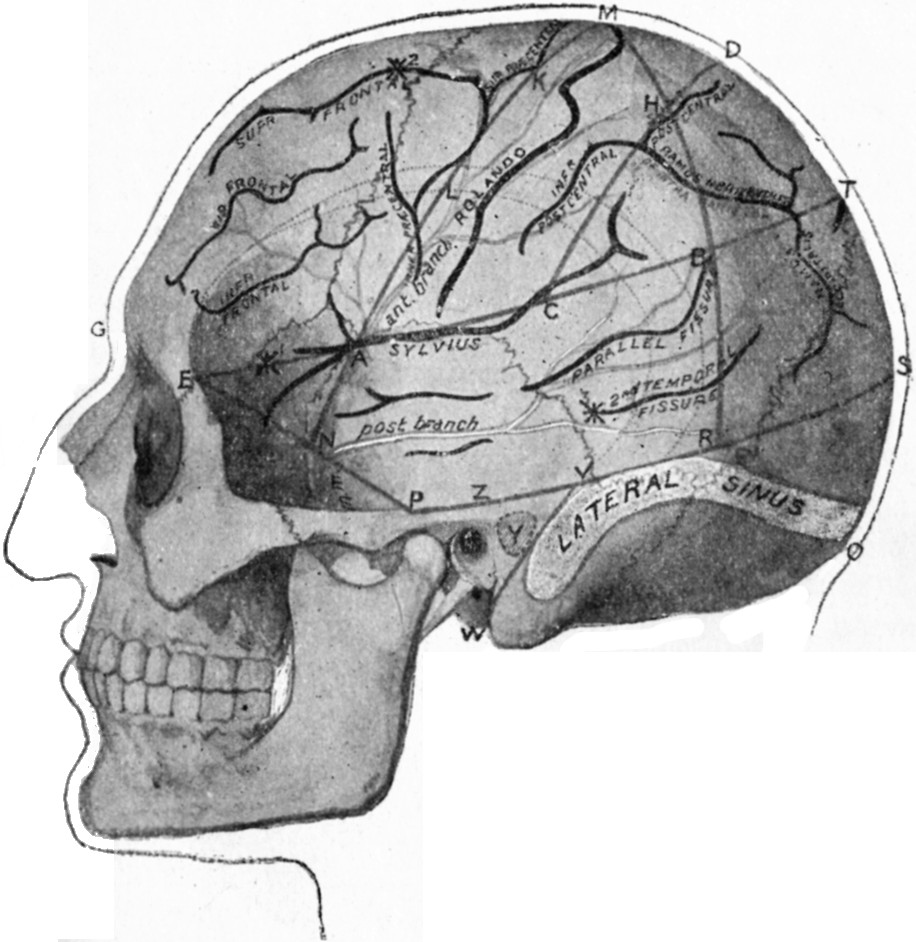

| 179. | Relations of the Motor and Sensory Areas to the Convolutions and to Chiene's Lines | 330 |

| 180. | Diagram of the Course of Motor and Sensory Nerve Fibres | 333 |

| 181. | Chiene's Method of Cerebral Localisation | 336 |